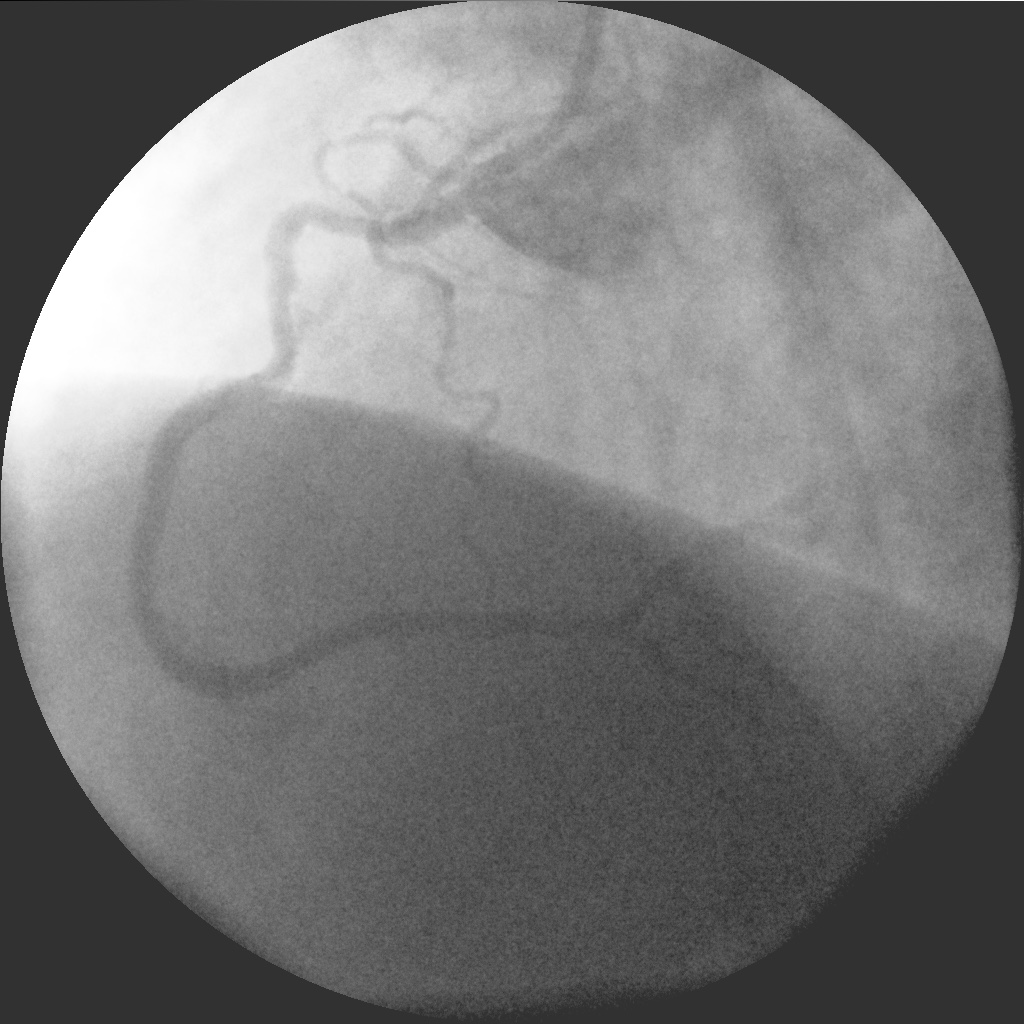

Позиционирование и стент в стент. Готово!

IM-0001-0021.jpg

IM-0001-0021.jpg [ 262.08 KiB | Просмотров: 51856 ]

IM-0001-0058.jpg

IM-0001-0058.jpg [ 227.83 KiB | Просмотров: 51856 ]